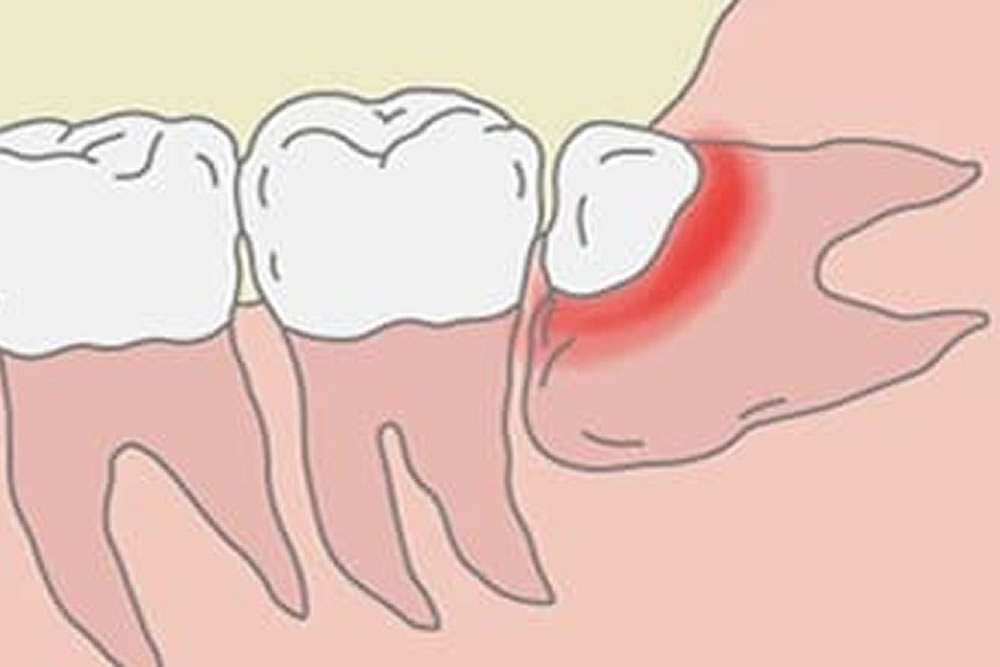

智歯周囲炎を繰り返す

歯茎から少しだけ顔を出している親知らずは、お手入れが難しく、汚れがたまりやすい状態です。そのため細菌が増えやすく、歯茎が腫れる「智歯周囲炎」を起こしやすくなります。症状が悪化すると、痛みや腫れに加えて、発熱や口が開きにくくなることもあるため、状態によっては抜歯をご提案することがあります。